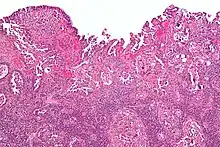

Micrograph of uterine serous carcinoma demonstrating characteristic psammoma bodies and cilia. H&E stain.

Characteristic discohesiveness of cells (like falling apart) around fibrovascular cores

Histopathologically, uterine serous carcinomas is typically characterized by (1) nipple-shaped structures (papillae) with fibrovascular cores (2) marked nuclear atypia (irregularities in the nuclear membrane, enlarged nuclear size), (3) psammoma bodies and (4) cilia.